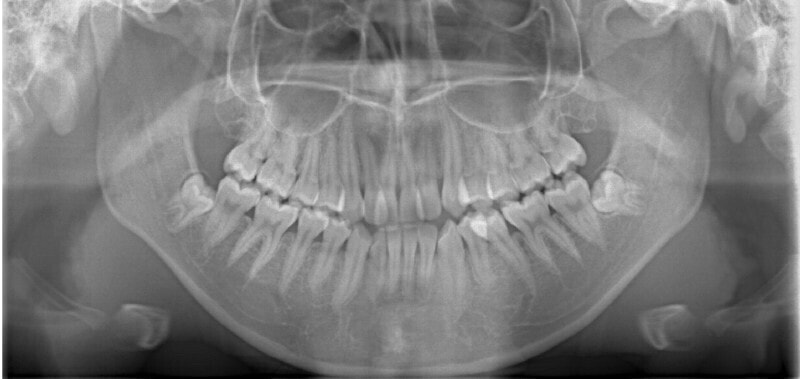

最診断時のセファロ分析:

リケッツ分析の統計上、男児は18才まで顔面の成長があるので、それまで経過観察を行いました。

検査時に予測した通り、骨格的下顎前突の要素はあまり発現しないで済みました。一期治療で反対咬合を解消しておいたことと、舌などの機能訓練に真面目に取り組んでいただけたことも良い要因であったと思います。

外科矯正も回避できて、さらに非抜歯で本格矯正を行うことができると診断し、現在2期治療中です。

下顎前突症例によくある顕著な顔面非対称もなく、幅径も良好な状態です。

少し大臼歯の傾斜が認められます。

上顎8番は先天欠如、下顎8番は埋伏しております。

歯根のパラレリング(平行性)も悪くなく、上顎洞、顎関節にも異常所見はありません。

セサモイドボーンも認められ、家族歴からも、今後の旺盛な下顎の成長の恐れがないと思われる所見です。